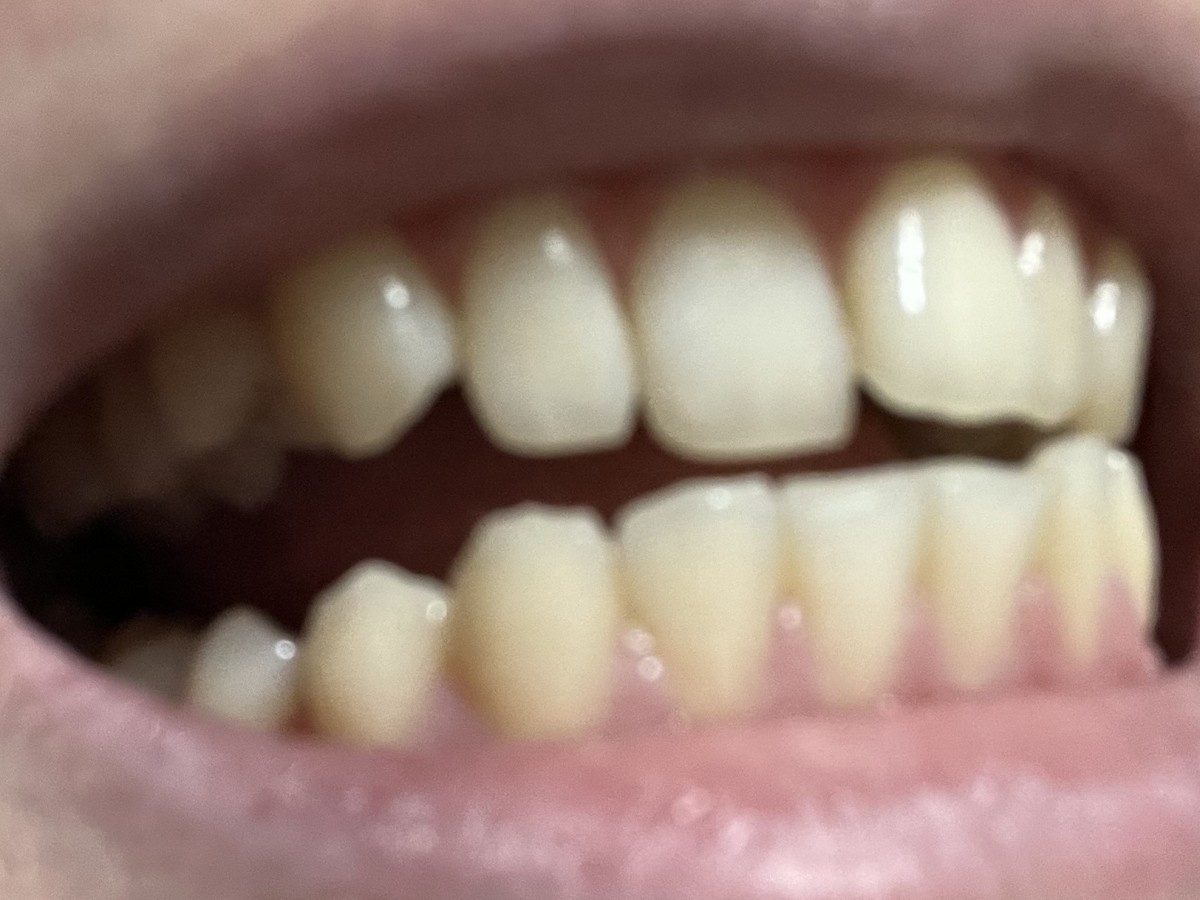

윗니 부분교정 문의

1. 발치없이 윗니만 부분교정 가능할까요?

2. 교정장치를 윗니쪽에만 부착하는지, 아랫니쪽에도 부착하게되나요?